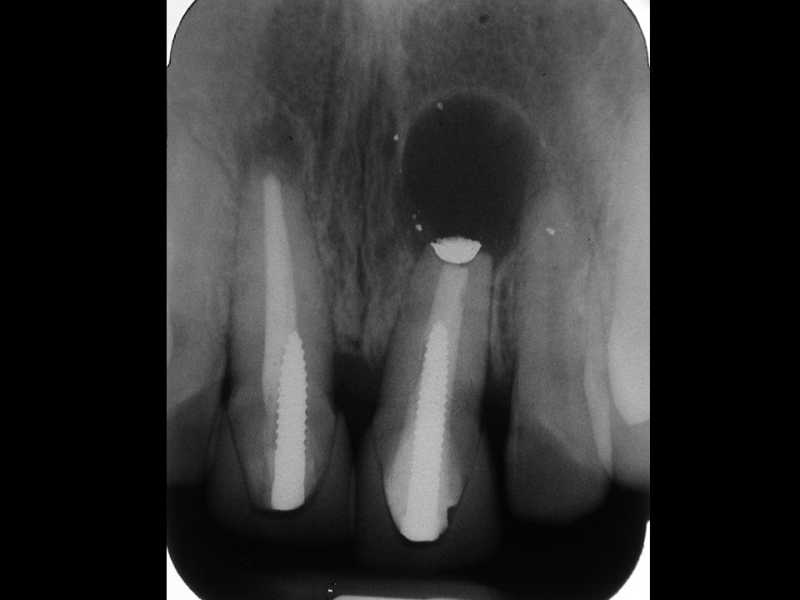

Inicio Especialidades Endodontia